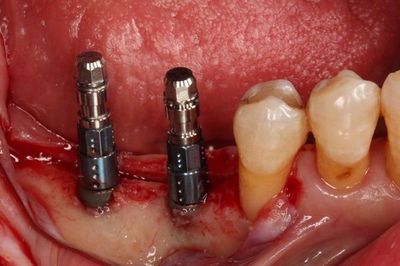

インプラントの埋入を終えました。

別アングルです。

スイスのストローマン社 ボーンレベルインプラントSLActive RCΦ4.1mm 10mm(手前用)

事前のシミュレーション通りの埋入を終えました。

スレッド(インプラント表面の螺旋ネジ構造表面)が露出している部分には

この後、骨切削片を置いて処置をします。